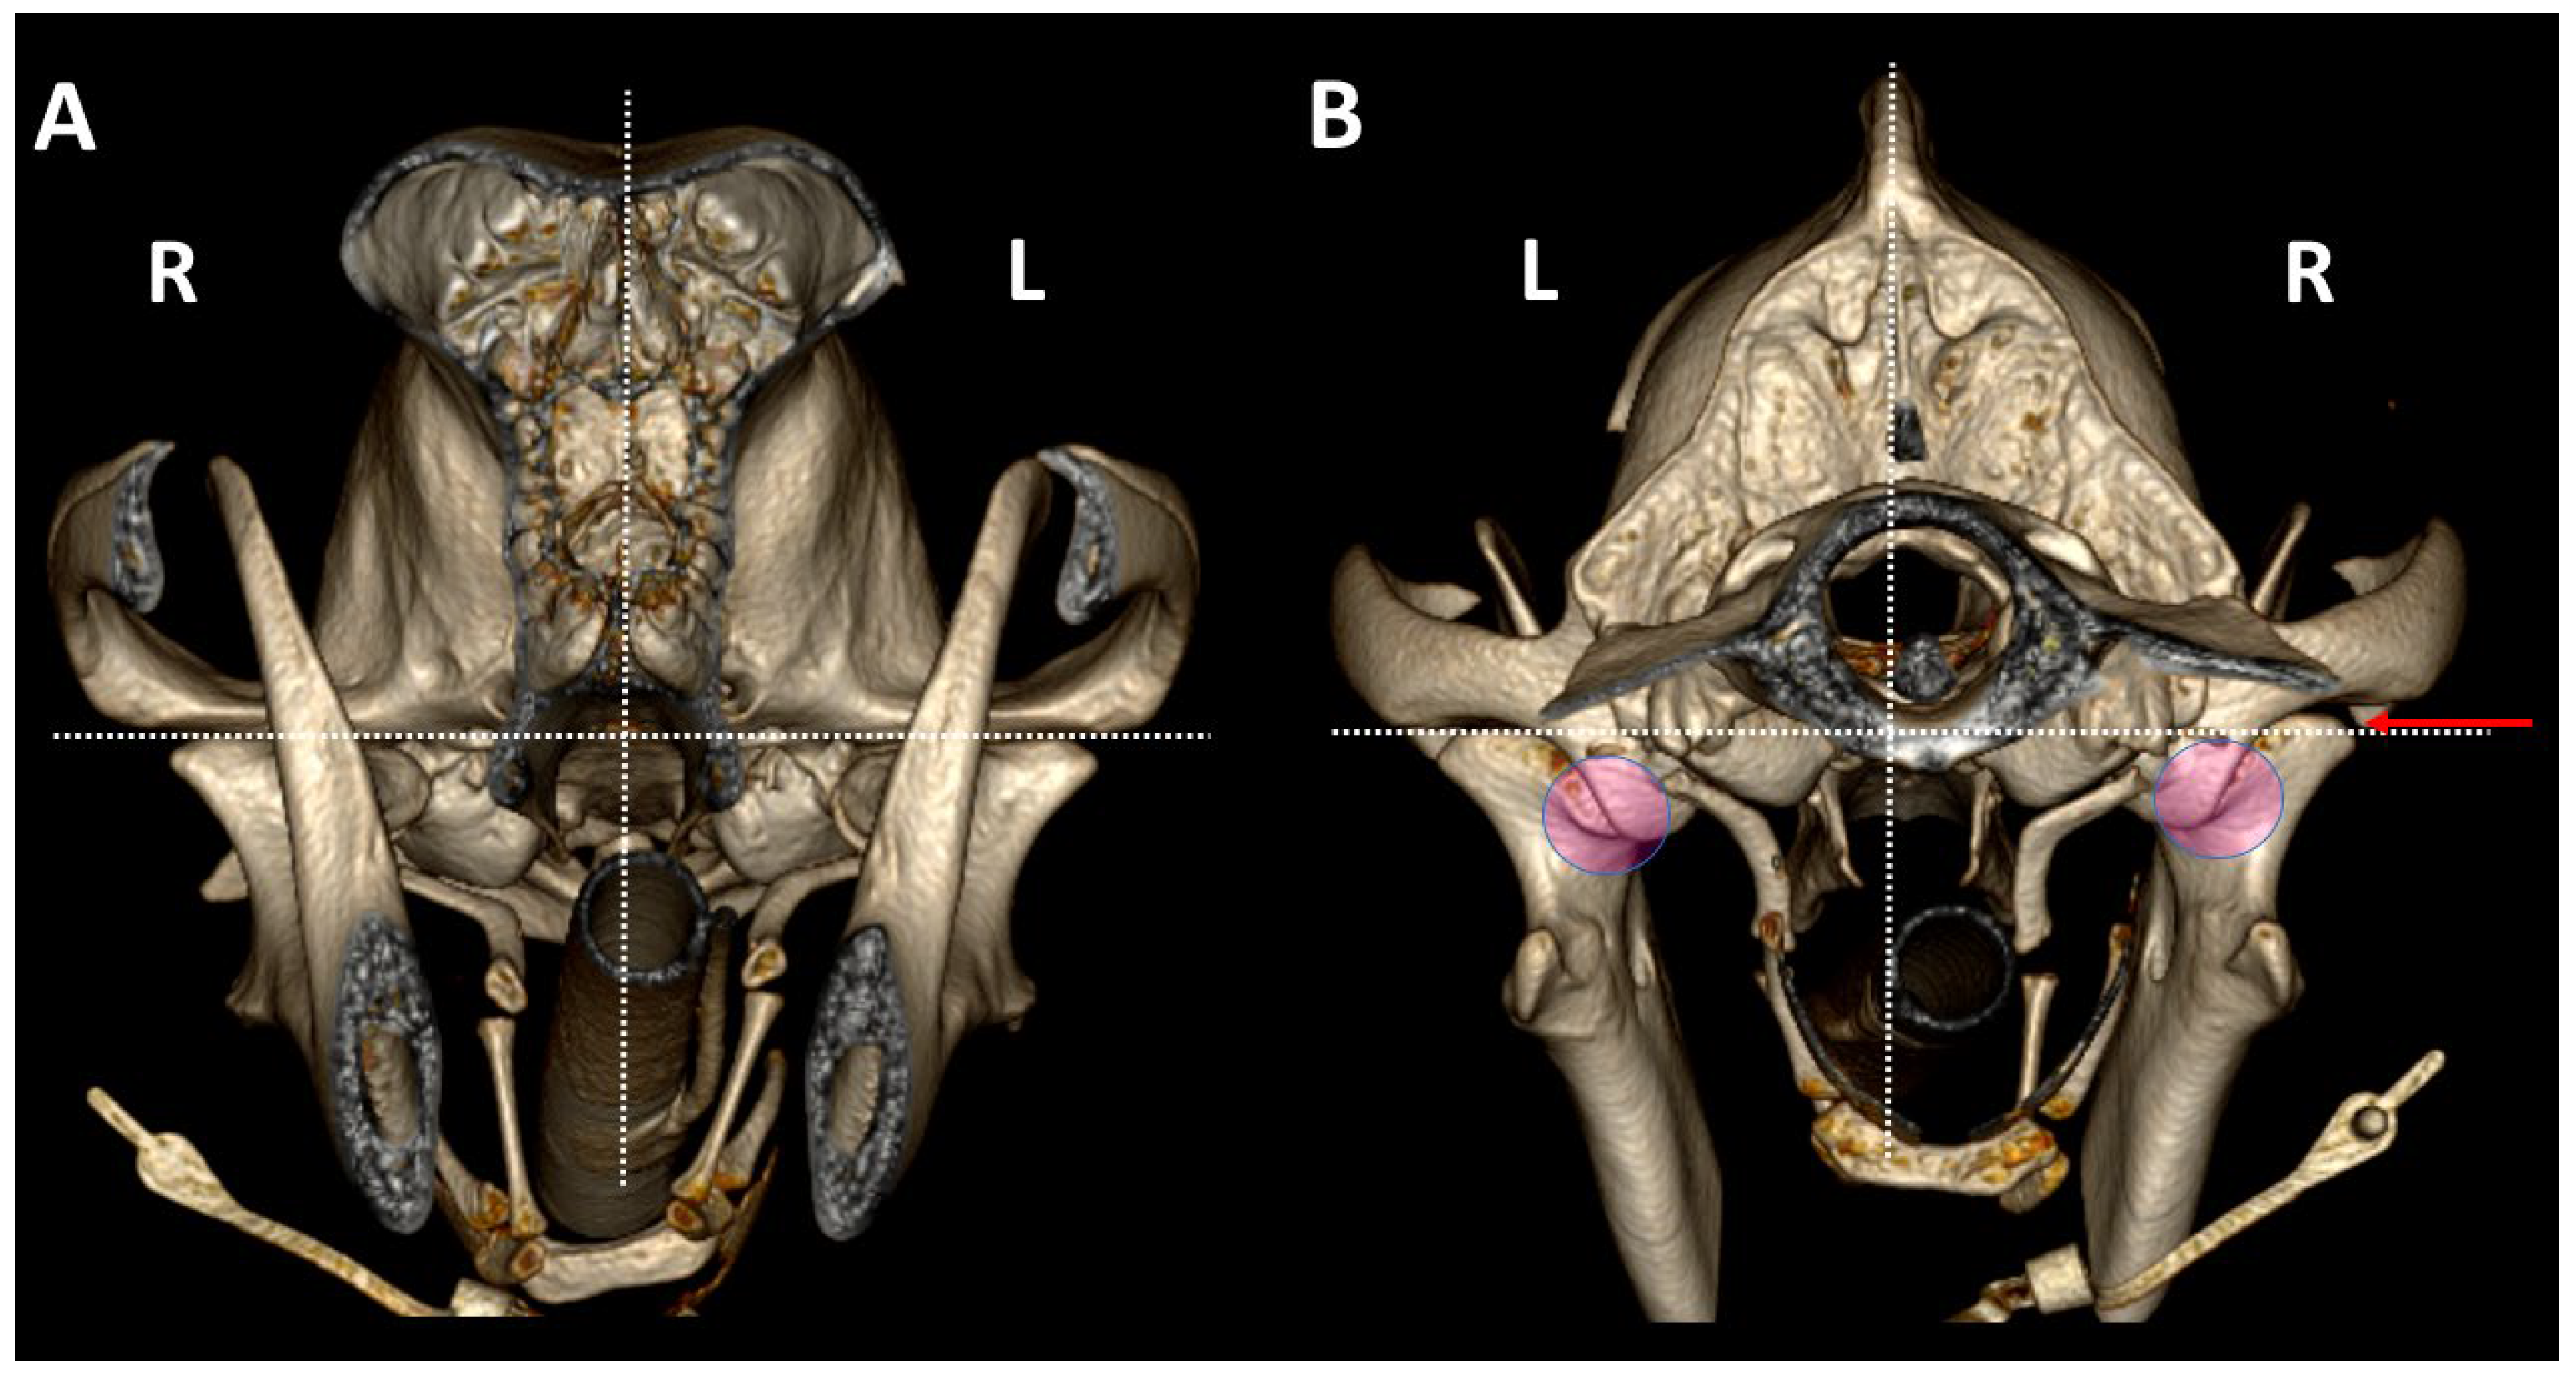

3.2. Comparison by 3DVR of TMJs in Each Dog, According to Skull Type and Age